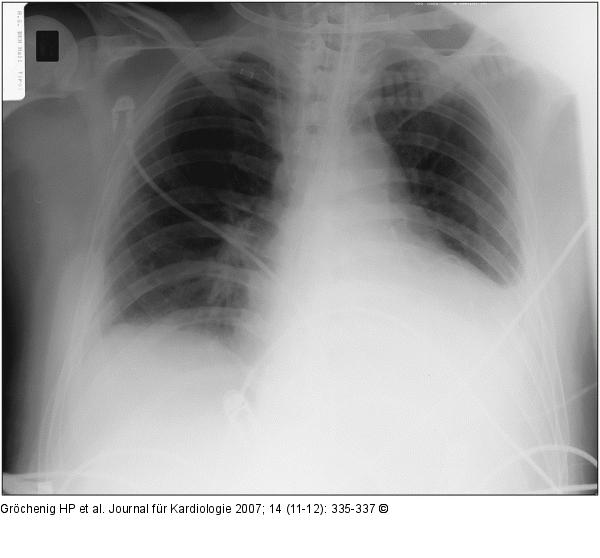

Abbildung 3: Thoraxröntgen Thoraxröntgen nach Drainage |